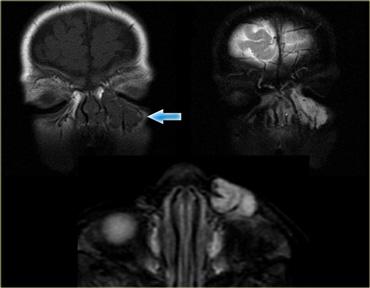

Bên trái là hình ảnh của một bệnh nhân khác với tổn thương ngoài nhãn cầu trong nón cơ.

Hãy quan sát hình ảnh, mô tả và đưa ra chẩn đoán phân biệt (tạm thời bỏ qua tiêu đề của đoạn này là u màng não).Các thần kinh thị giác bình thường, nhưng có hình ảnh ngấm thuốc dạng khối bất thường của bao thần kinh thị giác bên trái.

Do đó đây có thể là một u tân sinh, và trong số các u tân sinh, u màng não là u bao thần kinh thị giác phổ biến nhất.

U màng não biểu hiện rối loạn thị giác sớm trong quá trình bệnh do bệnh lý thần kinh thiếu máu cục bộ gây ra bởi tắc nghẽn tĩnh mạch.

Về mặt lâm sàng, biểu hiện này là đĩa thị nhợt nhạt.Ngấm thuốc bất thường của bao thần kinh thị giác

Bên trái là bảng chẩn đoán phân biệt của tình trạng ngấm thuốc bất thường bao thần kinh thị giác, còn được gọi là

dấu hiệu đường ray xe điện (tram track sign) của thần kinh thị giác.

U màng não của bao thần kinh là kết quả của sự phát triển dưới màng cứng dẫn đến mất thị lực tiến triển, phù gai thị, teo thần kinh thị giác.

Có mối liên quan chặt chẽ với bệnh u xơ thần kinh type 2 (NF-2).

Đĩa thị nhợt nhạt là do suy giảm dẫn lưu tĩnh mạch.

Vôi hóa được ghi nhận trong 20-50% trường hợp.

Gieo rắc vào khoang dưới nhện là một nguyên nhân khác gây ngấm thuốc bất thường của bao thần kinh thị giác, do bao thần kinh thị giác thông với khoang dưới nhện nội sọ.U thần kinh đệm thị giác